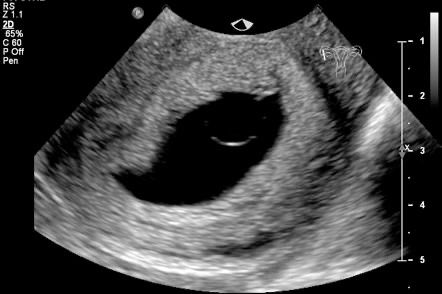

Q.11. What's the finding on USG?

Correct Answer : A

Q.12. What's the finding on USG?

Correct Answer : D

Q.13. What's the finding on USG?

Correct Answer : C